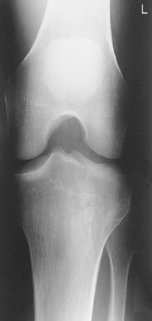

• Supine, or seated on table, with leg extended and centered to CR and midline of table or IR

• Rotate leg slightly inward as needed to place knee and leg into a true AP. Center IR to CR.

Medial oblique: Demonstrates fibular head and neck unobscured. (Lateral oblique may also be taken.)